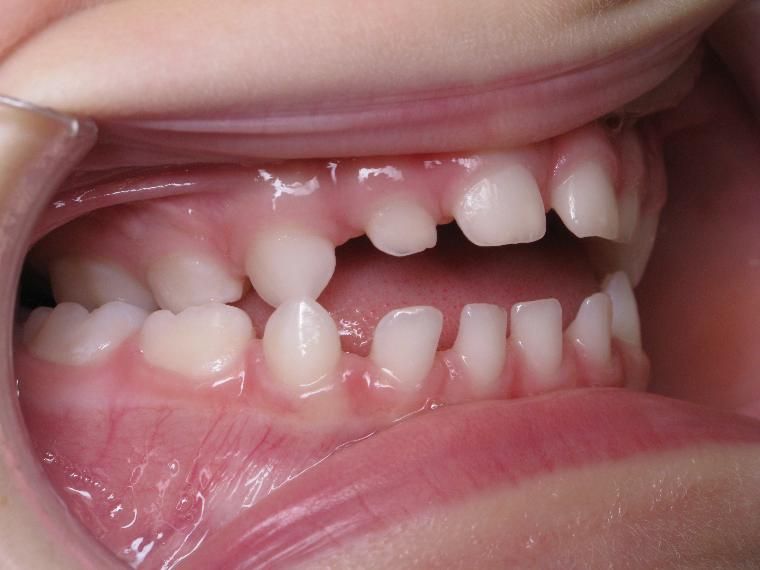

appareillage mobile pendant 35 mois

surveillance évolution de la dentition pendant 5 ans